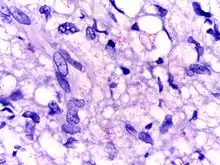

| Microphotograph of Mycobacterium leprae taken from a skin lesion. The small brick-red rod-shaped cells appear in clusters. Source: CDC | |